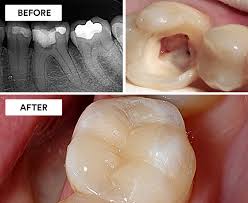

Dental Abscess Treatment

A dental abscess is a localized collection of pus, commonly caused by bacterial infection from tooth decay, broken teeth, periodontal disease, or failed root canal treatment. Timely treatment is essential to prevent further complications and restore oral health.

Before And After Treatment